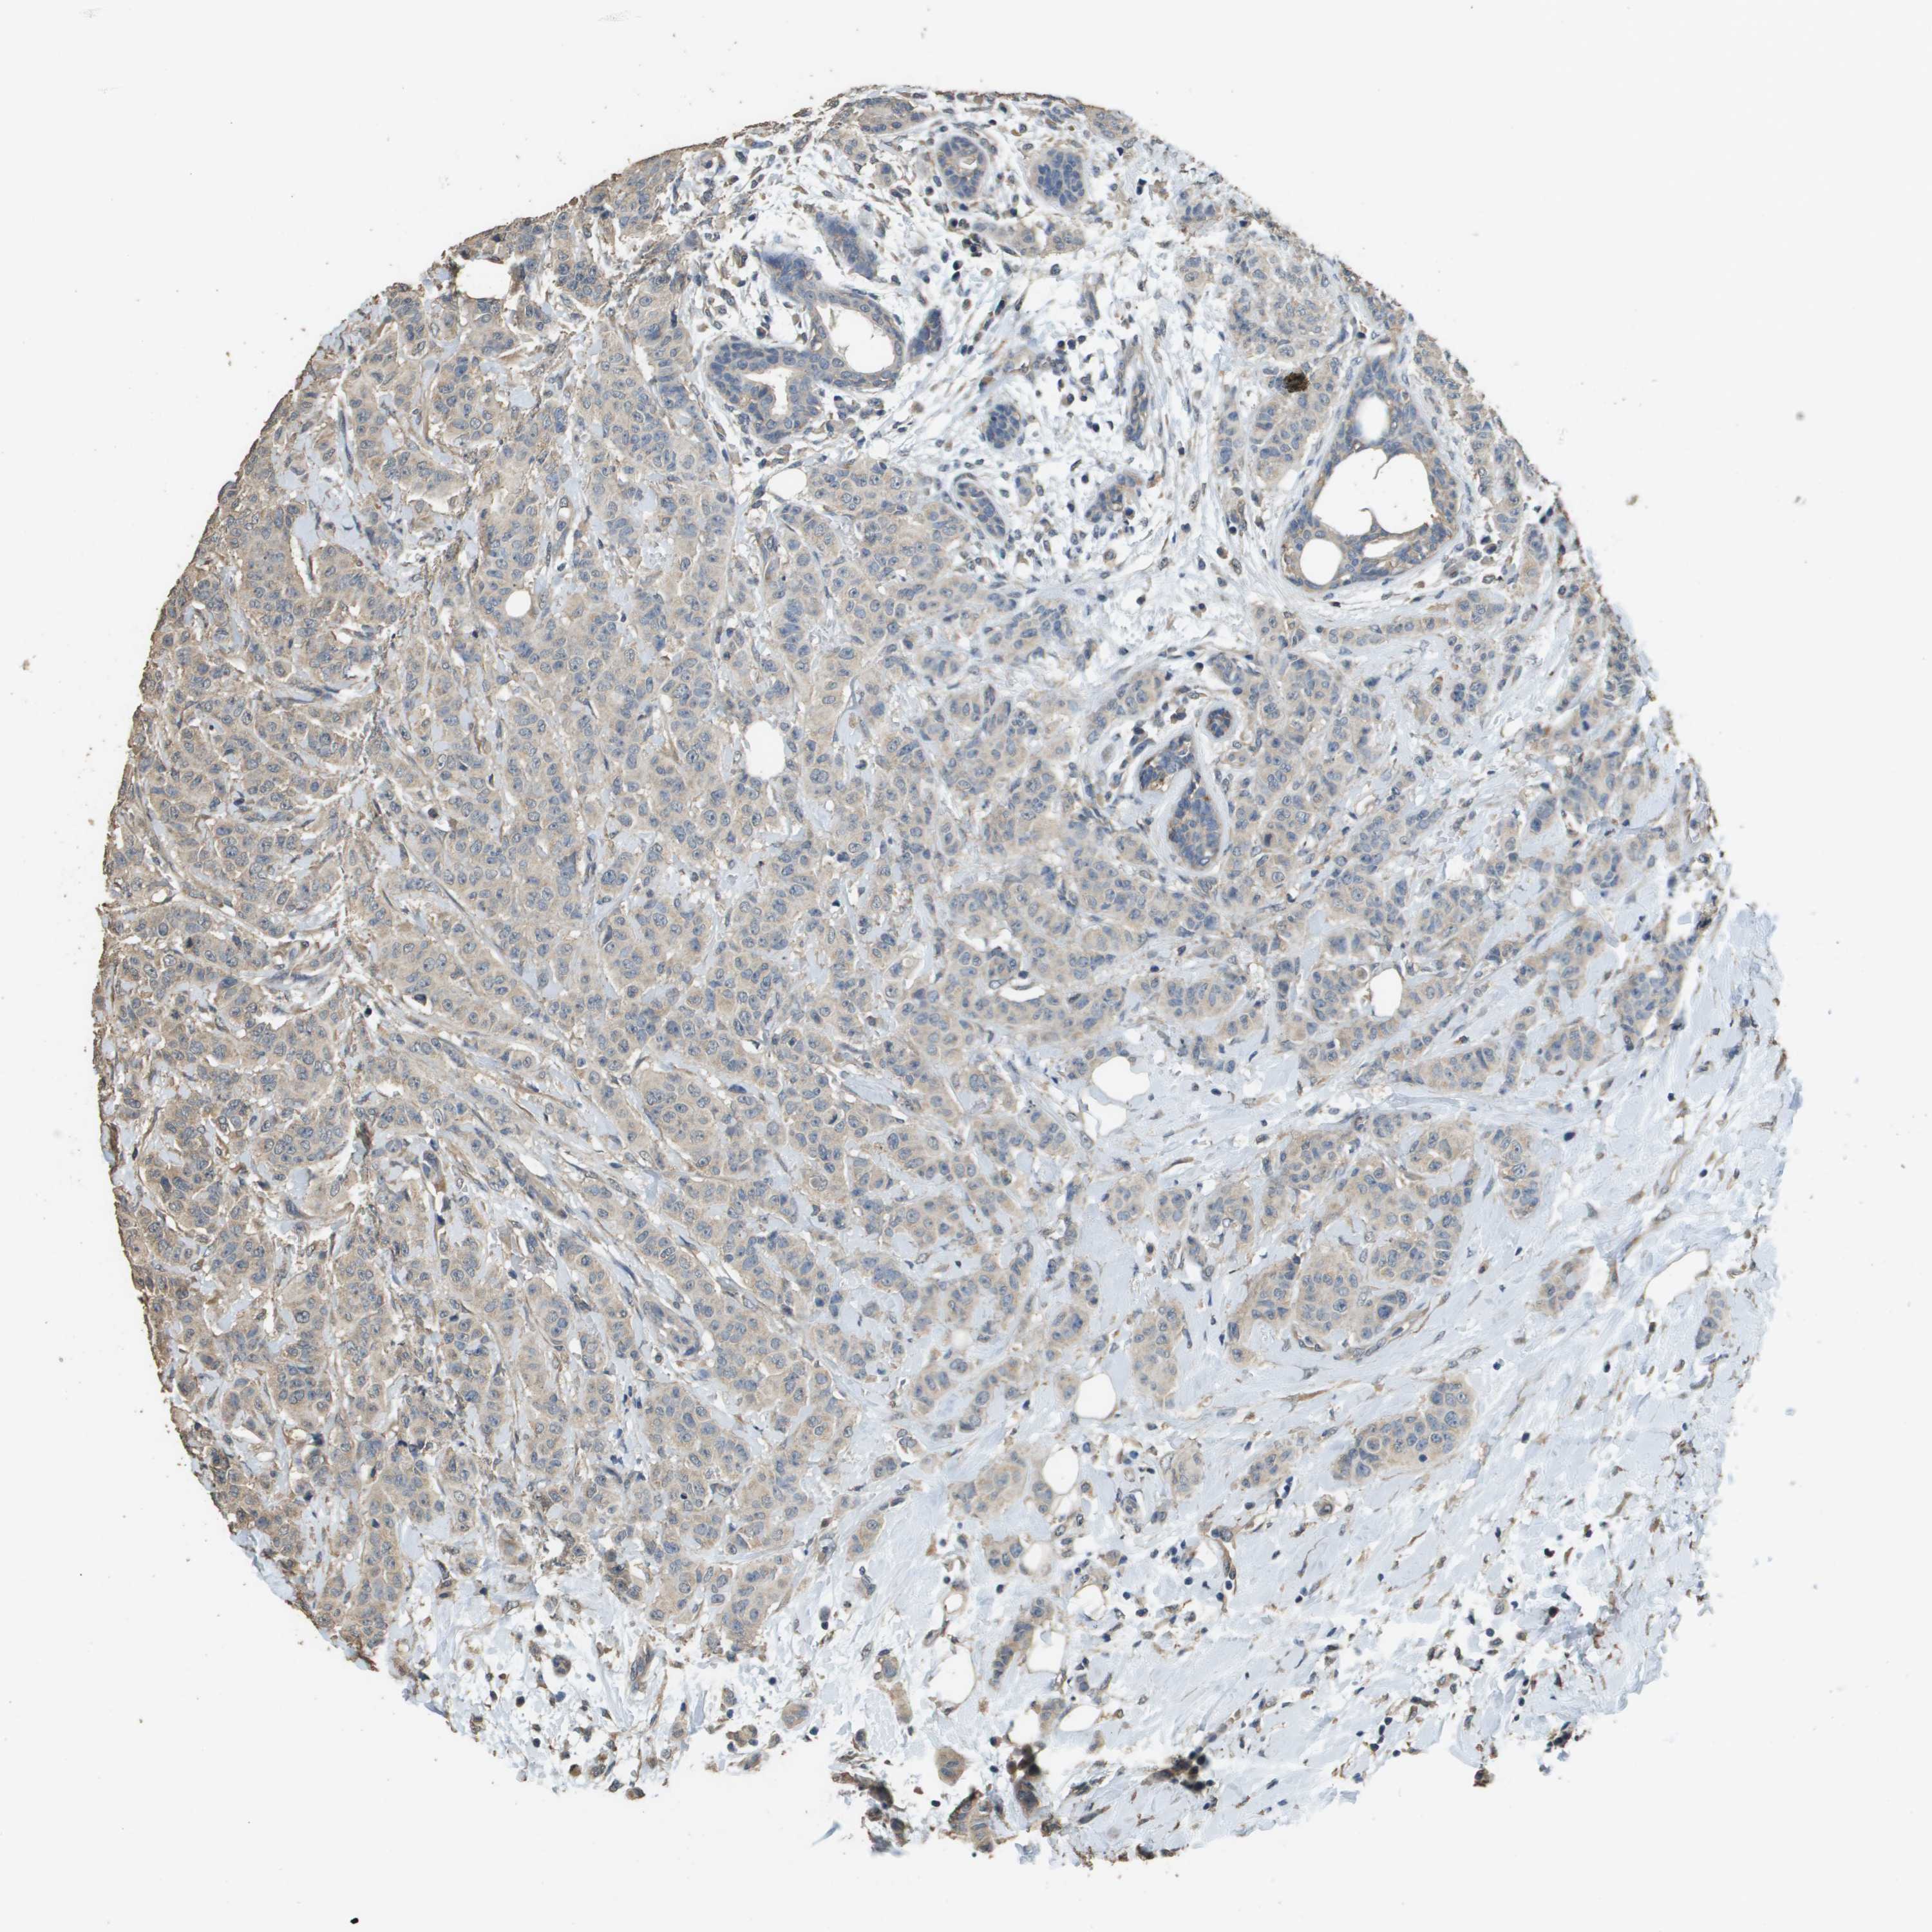

CANCER BREAST CANCER Show tissue menu

BRCA TCGA BRCA VALIDATION PROTEIN EXPRESSION